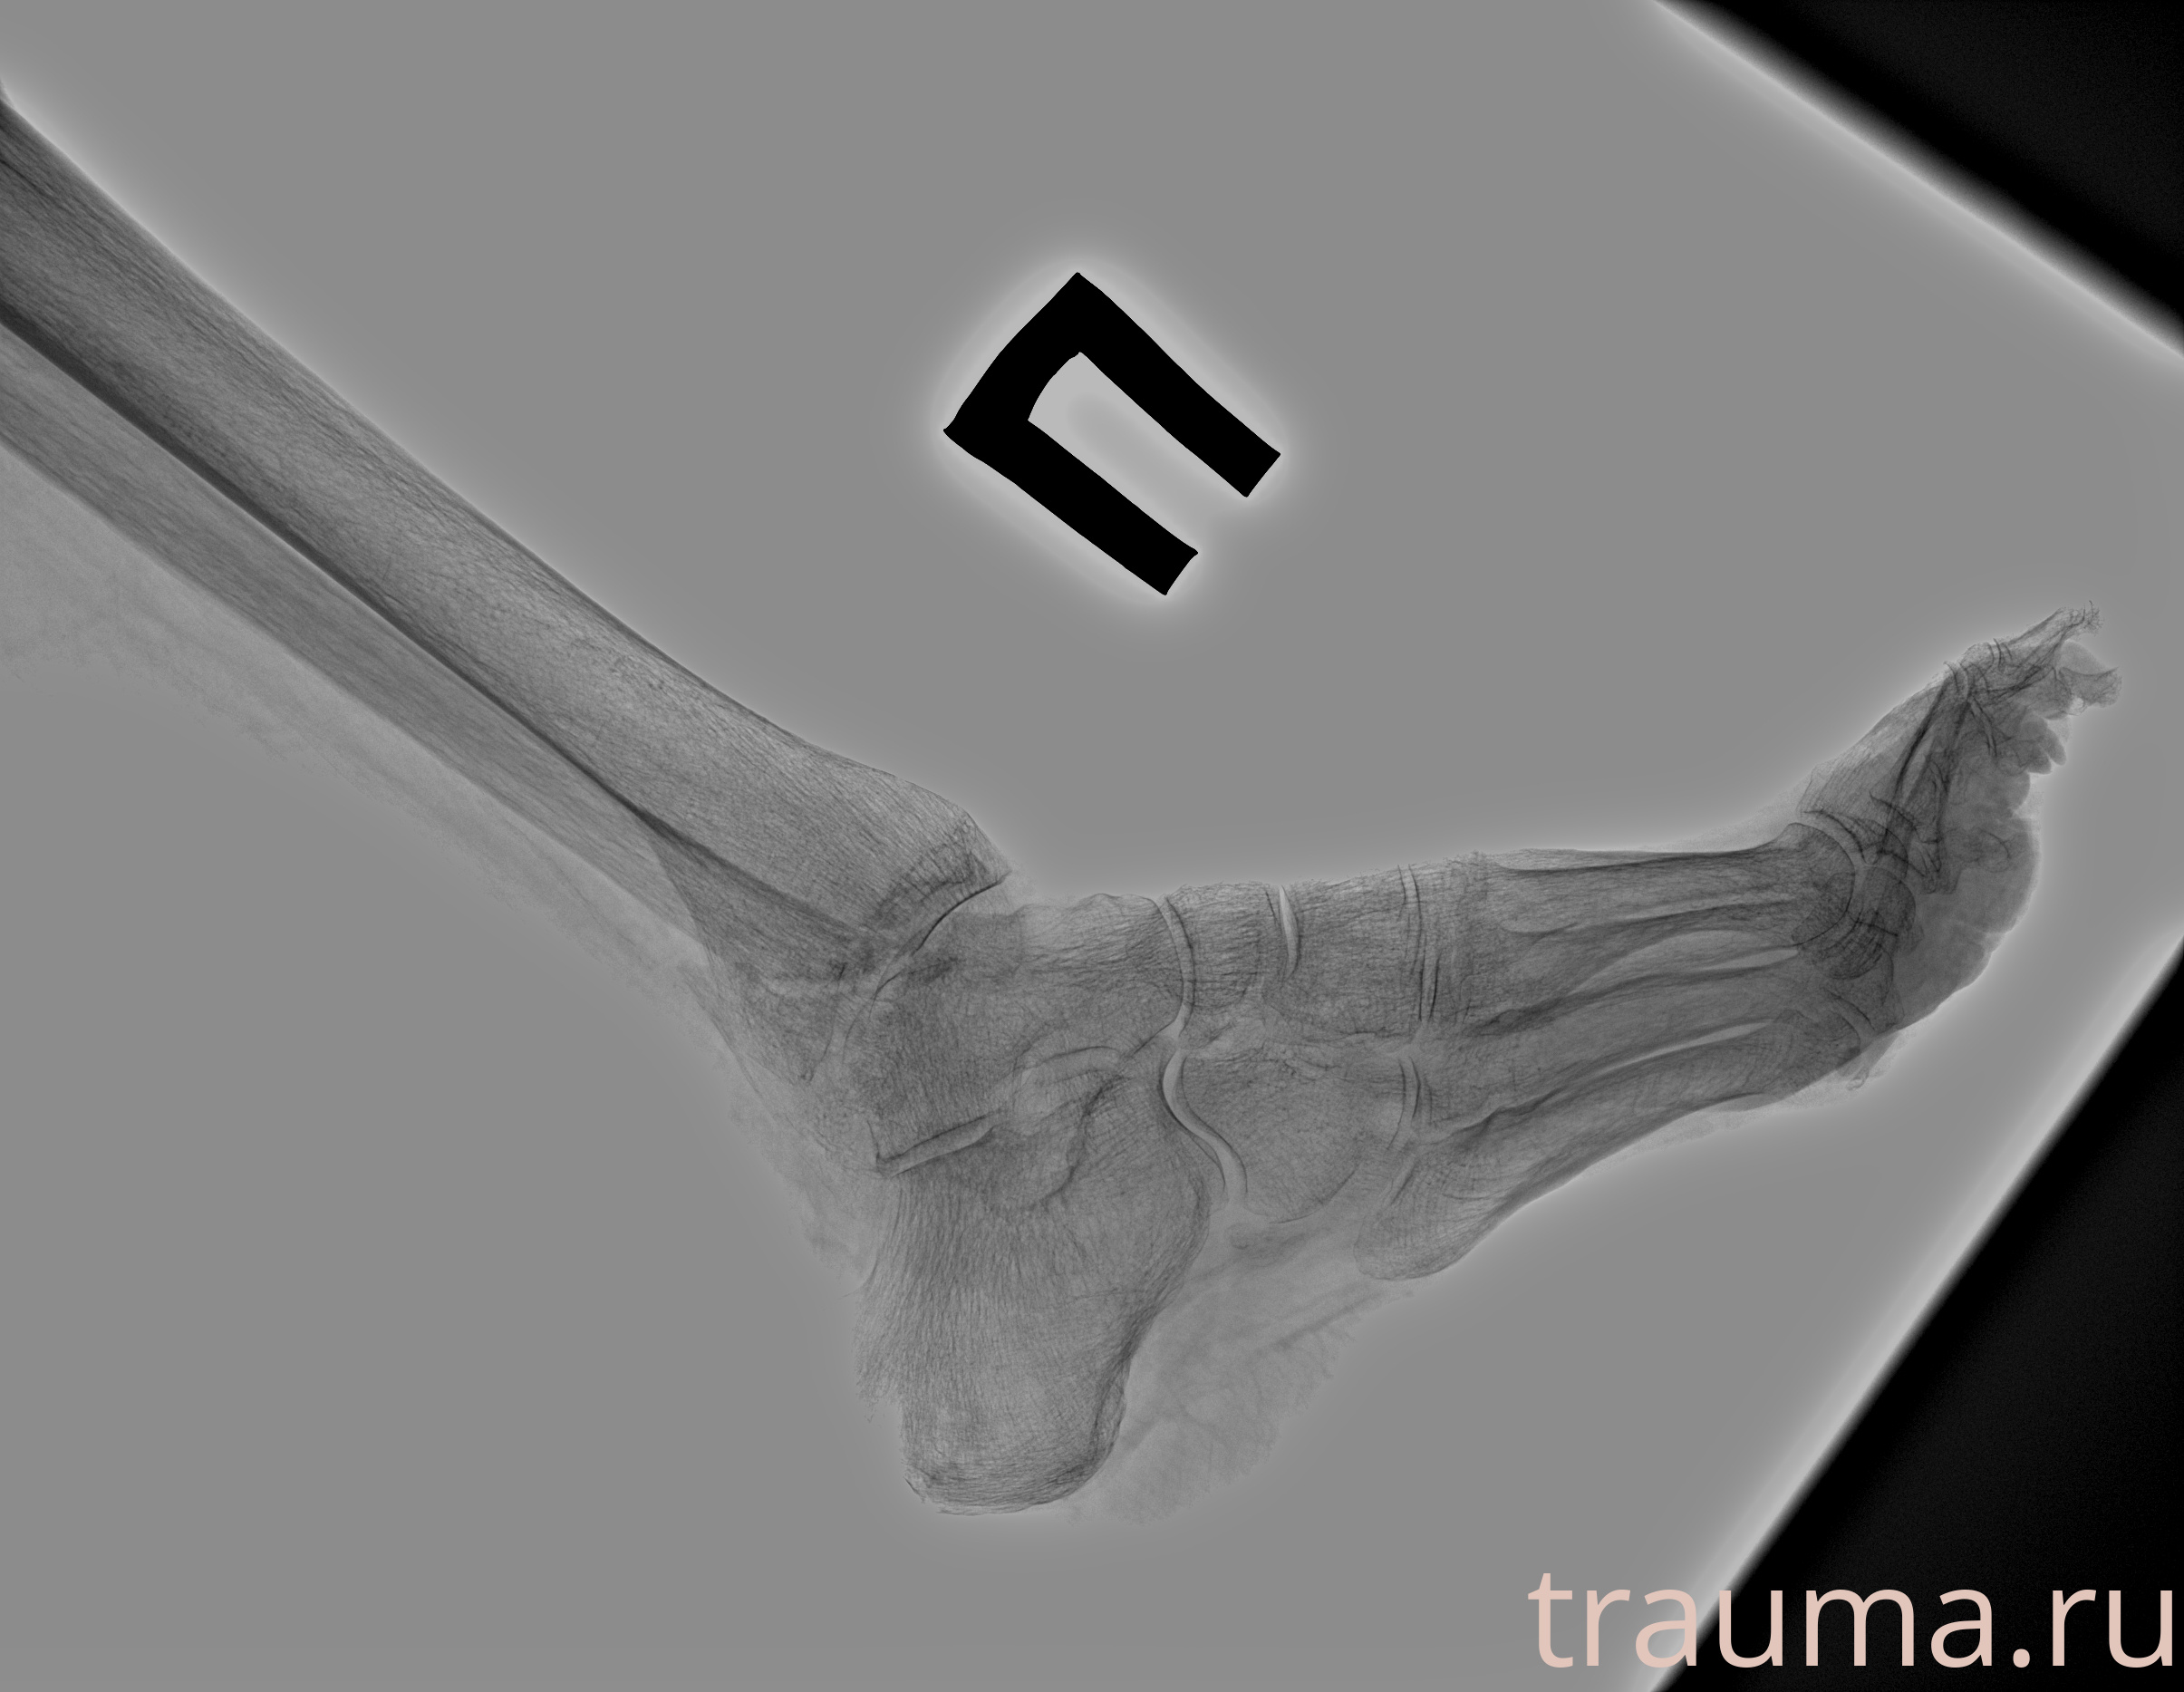

Рентген на дому: по вашему адресу приезжает врач-рентгенолог, травматолог-ортопед с мобильным рентгеновским аппаратом, проводит диагностику травмы или заболевания, делает необходимые рентгенограммы, дает рекомендации по дальнейшему лечению. Получить качественные снимки в домашних условиях возможно благодаря уникальной методике, разработанной МосРентген Центром для института  Склифосовского